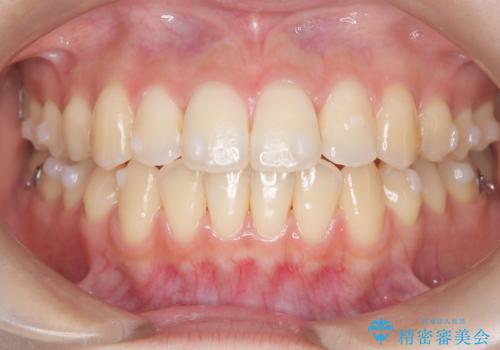

前歯のデコボコと突出を、目立たない矯正で解消

- 前歯のガタガタ(叢生)と、前歯が出ている(突出している)ことを気にされてご来院されました。精密な検査の結果、歯が並ぶスペースと、前歯を引っ込めるスペースの両方が不足していると診断。患者様のご希望に合わせ、透明で目立ちにくいインビザライン(マウスピース矯正)による治療計画を立案しました。スペースの確保は、奥歯全体を奥へ動かす遠心移動と、歯の側面をわずかに削る**IPR(歯間乳頭保護下ストリッピング)**を組み合わせて行い、前歯を効果的に引っ込めることを目指します。

今回の矯正治療では、透明なマウスピース型の装置インビザラインを使用しました。前歯を無理なく引っ込めるスペースを作るため、まず奥歯全体を後方へ移動させる遠心移動を実施。さらに、安全性が確保できる範囲で歯の側面をわずかに削るIPRを併用し、必要なスペースを確保しました。これらの処置により、前歯のデコボコが解消され、前に出ていた前歯も適切に引っ込みました。目立たない装置で治療を完結することで、叢生と突出感が解消され、機能性と審美性が向上した美しい口元を獲得していただけました。